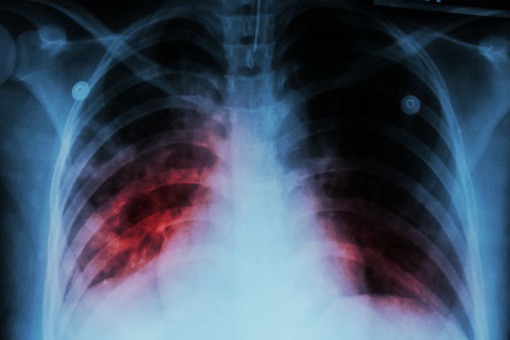

Respiratorowe zapalenie płuc w urazowym uszkodzeniu mózgu: zachorowalność i śmiertelność

Respiratorowe zapalenie płuc (VAP) występuje rzadziej niż wcześniej opisywano u intubowanych pacjentów po urazowym uszkodzeniu mózgu (TBI) i chociaż może mieć szkodliwy wpływ na długość pobytu na oddziale intensywnej terapii, nie wydaje się by mogło mieć taki sam wpływ na wyniki neurologiczne i śmiertelność.